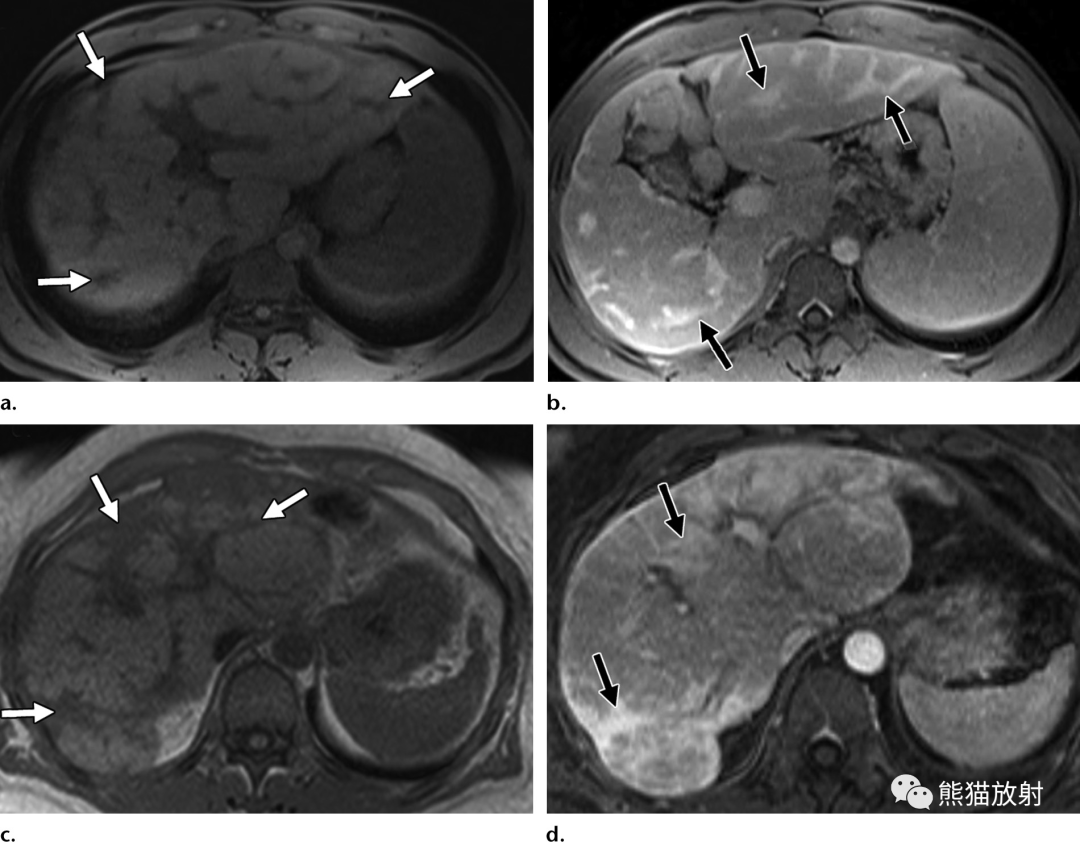

血吸虫病与自身免疫性肝炎

(a,b) 42岁男性,肝血吸虫病。(a) 脂肪抑制T1WI图像显示厚的低信号纤维间隔(箭)。(b)对比增强脂肪抑制T1WI图像显示肝包膜下纤维带有强化(箭头)。

(c,d) 51岁女性,自身免疫性肝炎。(c) T1WI同相位图像显示肝包膜下纤维化,表现为较厚的带状影及低信号融合区(箭)。(d) 条片状纤维化区域延迟强化(箭头),与血吸虫病患者的影像表现相似。